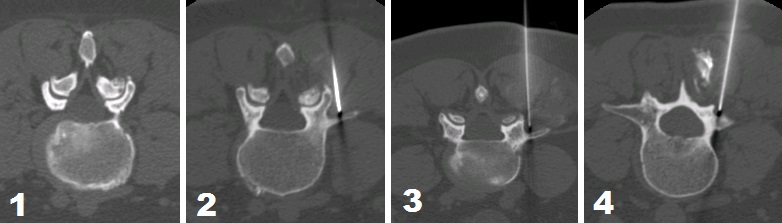

Quando sono state definite la o le articolazioni posteriori da trattare, si procede, mediante radiofrequenza pulsata, al blocco selettivo della branca mediale del ramo posteriore del nervo lombare del livello individuato, di quello superiore e di quello inferiore. Il posizionamento dell'agoelettrodo da 20 G si effettua con estrema precisione con guida TC (si vedano le fig. 1, 2, 3 e 4) e viene confermato dal test di stimolazione. L'utilizzo della RF pulsata consente di 'bloccare' solo le fibre sensitive del nervo, evitando di ledere quelle motorie poiché alla punta dell'agoelettrodo, posizionata a qualche millimetro dal nervo, si raggiunge una temperatura di circa 42°.

Figura 1 - Lo studio TC del rachide lombo-sacrale dimostra fenomeni degenerativi dell'articolazione posteriore di L4-5 a Ds.

Figura 2 - La scansione TC dimostra il corretto posizionamento della punta dell'agoelettrodo (20G) (confermato anche dal test di stimolazione) in prossimità della branca mediale del ramo posteriore di L4.

Figura 3 - La scansione TC dimostra il corretto posizionamento della punta dell'agoelettrodo (20G) (confermato anche dal test di stimolazione) in prossimità della branca mediale del ramo posteriore di L3.

Figura 4 - La scansione TC dimostra il corretto posizionamento della punta dell'agoelettrodo (20G) (confermato anche dal test di stimolazione) in prossimità della branca mediale del ramo posteriore di L5.